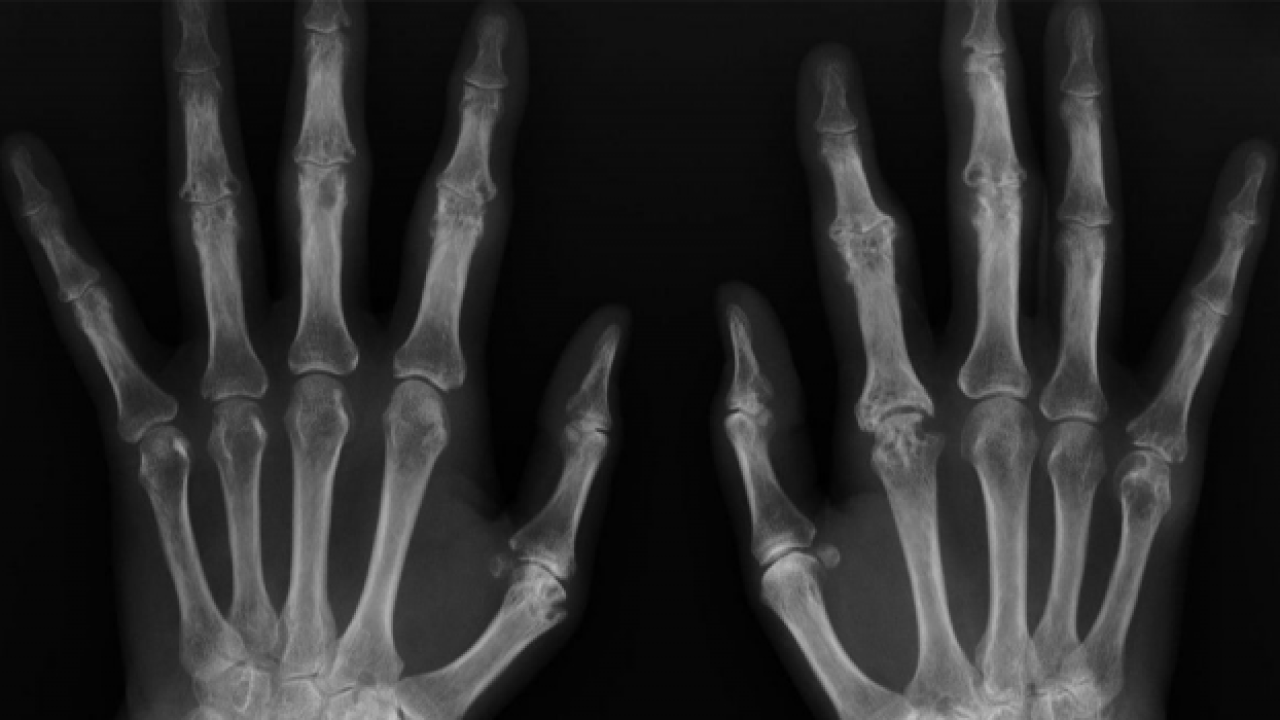

Akademisyenler, kemik yaşını yapay zeka ile bir dakikanın altında sürede tespit edecek sistem geliştirdi.

Siirt Üniversitesi Öğretim Üyesi Doç. Dr. Yılmaz Kaya'nın, iki akademisyenin desteğiyle geliştirdiği, sol el bilek grafisinden kemik yaşı tespitine ilişkin sistemle ilgili makalesi uluslararası dergide yayınlandı.

Çalışmalarıyla, Stanford Üniversitesi bilim insanlarından Prof. Dr. John P. A. Loannidis ve ekibince hazırlanan, Plos Biology Dergisi'nde yayınlanan "Dünyanın en etkili bilim insanları" listesinde 2020 ve 2021 yılında yer alan Siirt Üniversitesi (SİÜ) Mühendislik Fakültesi Bilgisayar Mühendisliği Bölümü Öğretim Üyesi Doç. Dr. Yılmaz Kaya öncülüğünde yapılan sol el bilek grafisinden kemik yaşı tespitine yönelik çalışmalar sonuçlandı.

Kaya'nın SİÜ Teknik Bilimler Meslek Yüksekokulunda Öğretim Görevlisi Cüneyt Özdemir ve Kütahya Sağlık Bilimleri Üniversitesi Evliya Çelebi Eğitim ve Araştırma Hastanesi Radyoloji Uzm. Dr. Mehmet Ali Gedik ile derin öğrenme teknolojisi kullanarak geliştirdiği sistem ile ilgili hazırlanan makale uluslararası kabul gören dergilerden "Traitement du Signal"de yayınlandı.

Akademisyenler yapay zekanın en önemli konularından olan derin öğrenme metotları ile çalışan sistemle ilgili bir de web sitesi oluşturdu.

Herhangi bir gerekçe ile kişinin kemik yaşı tespiti gerektiğinde el bilek görüntüsü sisteme yüklenerek, bir dakikanın altında sürede tespit yapılabilecek.

Bu kapsamda akademisyenler Özdemir ve Gedik ile yaptıkları çalışmada kemik yaşı tahmini için radyologların iş akışını hızlandıracak bir çalışma yürüttüklerini ifade eden Kaya, sol el bilek grafisinden derin öğrenme teknolojisi kullanılarak bilgisayar temelli bir karar destek sistemi geliştirdiklerini belirtti.

Verileri Kütahya'daki 4 hastaneden elde ettiklerini dile getiren Kaya, "Yapay zeka tekniklerini kullanarak el grafilerinden kişinin yaşını tespit etmeye çalıştık. Yaş tespiti çok zahmetli bir şekilde radyologlar tarafından belirleniyor ama bilgisayar sistemiyle çok daha kolay ve hızlı şekilde gerçekleştirebilirsiniz." dedi.

Kaya, el grafisinden kemik yaşı tespitinin daha önce yaklaşık 2 saat sürdüğüne işaret ederek, geliştirdikleri sistemle yaş tespit süresinin saniyelere düştüğünü kaydetti.

"Geliştirdiğimiz sistemle paket program halinde veya web sitesi üzerinden bu çalışmayı saniyelere indirebiliyoruz. Bu, özellikle radyologlar için destekleyici bir program. Bunu Türkiye'deki bütün hastanelere yaymak istiyoruz." diyen Kaya, bunun yanı sıra tüm Türkiye'nin el grafik atlasını da çıkarmaya çalıştıklarını aktardı.

Öğretim görevlisi Cüneyt Özdemir de derin öğrenme yöntemiyle sol el bilek grafisinden kemik yaşı tespitine yönelik çalışmaların 18 yaş altı ve 18 yaş üstü bireylere yönelik iki aşamadan oluştuğunu belirtti.

Özdemir, "Ülkemizde bu işlem için radyologlar genellikle gök atlası dediğimiz sistemden yararlanmakta. Bu yöntemde radyologlar bakış açılarına göre farklı sonuçlar da elde edebiliyorlar. Bu çalışmayla bu işlemi otomatikleştiren, radyologlar için bir karar destek sistemi geliştirdik. Bu sistem uzmanların iş akış sürecini hızlandırıp, kolaylaştıracak." diye konuştu.

18 yaş üstü bireylerin kemik yaşının tespitine yönelik de çalışma yaptıklarını aktaran Özdemir, "18 yaş üstü ile ilgili çalışmalar maalesef ülkemizde ve dünyada az. 18 yaş üstü kemik yaşı tespiti için yüz ve dişlerle ilgili yapılan çalışmalar var. Biz ilk defa el bilek grafisinden 18 yaş üstü kemik yaşının tespitine dönük de bir çalışma yaptık. Bu yöntemle başarılı bir sonuç elde ettik. Bu, literatürde derin öğrenme yöntemiyle 18 yaş üstü kişilerin kemik yaşı tespitine dönük yapılan ilk çalışmalardan biri olma özelliğini taşıyor." ifadelerini kullandı.